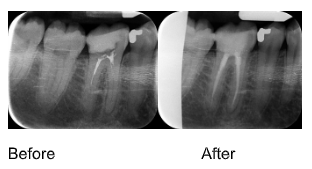

Treatment Results

Before & After X-rays

View examples of successful endodontic treatments demonstrating the precision and effectiveness of our root canal therapy.